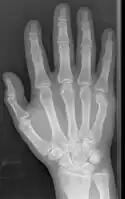

Diagnosis by a doctor’s examination is the most common, often confirmed by x-rays. X-ray is used to display the fracture and the angulations of the fracture. A CT scan may be done in very rare cases to provide a more detailed picture.[8]

Boxer fracture

Boxer fracture of the 4th and 5th knuckles